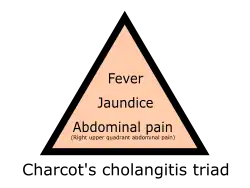

Physical examination findings typically include jaundice and right upper quadrant tenderness.[1] Charcot's triad is a set of three common findings in cholangitis: abdominal pain, jaundice, and fever.[4] This was assumed in the past to be present in 50–70% of cases, although more recently the frequency has been reported as 15–20%.[1] Reynolds' pentad includes the findings of Charcot's triad with the presence of septic shock and mental confusion.[5] This combination of symptoms indicates worsening of the condition and the development of sepsis, and is seen less commonly still.[1][2]

Dr Jean-Martin Charcot, working at the Salpêtrière Hospital in Paris, France, is credited with early reports of cholangitis, as well as his eponymous triad, in 1877.[4] He referred to the condition as "hepatic fever" (fièvre hépatique).[4][7] Dr Benedict M. Reynolds, an American surgeon, reignited interest in the condition in his 1959 report with colleague Dr Everett L. Dargan, and formulated the pentad that carries his name.[5] It remained a condition generally treated by surgeons, with exploration of the bile duct and excision of gallstones, until the ascendancy of ERCP in 1968.[26] ERCP is generally performed by internal medicine or gastroenterology specialists. In 1992 it was shown that ERCP was generally safer than surgical intervention in ascending cholangitis.[27]